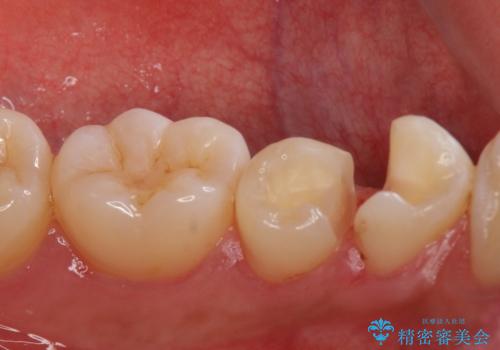

- 矯正前の患者様です。検査により虫歯がありましたのでe-maxインレー治療を行いました。

- e-maxインレー 7.7万×2費用は治療当時の料金となります